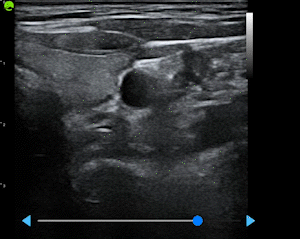

View Recognition & Validation

AI identifies and validates standard cardiac and OBG views, ensuring protocol compliance

Built from a dataset of millions de-identified ultrasound images, our AI models cover Obstetrics, Cardiology, and Gynecology. They analyze key anatomical structures in real time, providing accurate biometric measurements and insights that help clinicians assess fetal growth, cardiac function, and organ health with greater speed and confidence.